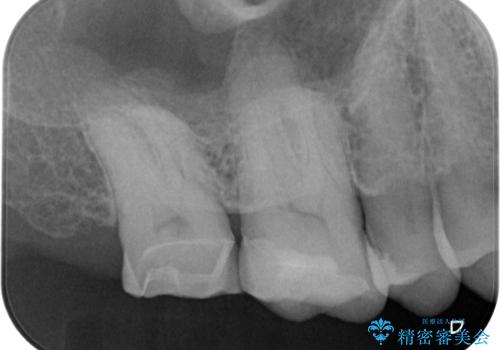

虫歯が詰め物の下で広がっていたこと、もともとの詰め物が大きく健全な歯の量が少なく噛む面に強い力がかかったことが原因で歯が欠けてしまった事が考えられます。

精査の結果、歯肉縁下に破折は認めれられませんでした。

部分的な詰め物では再び割れてしまう可能性が高いため、虫歯を除去し、オールセラミッククラウンにて補綴することとしました。